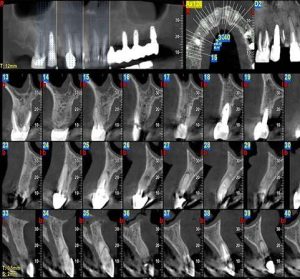

قياس طول العظام باستخدام التصوير المقطعي المحوسب المخروطية لوضع الزرعة

يُستخدم التصوير المقطعي المحوسب المخروطيّ (CBCT) على نطاق واسع لقياس طول عظم الفك والتخطيط الدقيق لزراعة الأسنان. تتيح هذه الطريقة لطبيب الأسنان رؤية وتحليل بنية العظم بشكل ثلاثي الأبعاد، وتحديد الحجم والموضع المناسبين للزراعة.

فحص أسنان بسيط OPG

التصوير الشعاعي البانورامي (OPG) هو إجراء تصوير بالأشعة السينية يُظهر رؤية كاملة للأسنان والفكين العلوي والسفلي والأنسجة المحيطة بها في صورة واحدة. يُستخدم لفحص وتشخيص مشاكل الأسنان، مثل التسوس الشديد، والأسنان المطمورة، وكسور الفك، وأمراض اللثة، وتشوهات الأسنان.